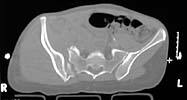

A woman in her 30's in a high speed MVC with this closed pelvic fracture. She's hemodynamically stable, no other injuries - belly, chest, and head are all fine. She also has a comminuted supracondylar femur fracture on the R side.

Preop CT

the enclosed ct image demonstrates her second, not upper sacral segment.

her plain pelvic radiographs indicate upper sacral dysmorphism, which has a significant impact on safe iliosacral screw insertion, regardless of imaging modality chosen to assist insertion.

the ct image reveals no significant posterior pelvic degloving injury, for that single axial image.

the strategy relies on the other images which reveal the exact iliac fracture-sacroiliac disruption sites, local soft tissue condition, as well as the upper sacral morphology.